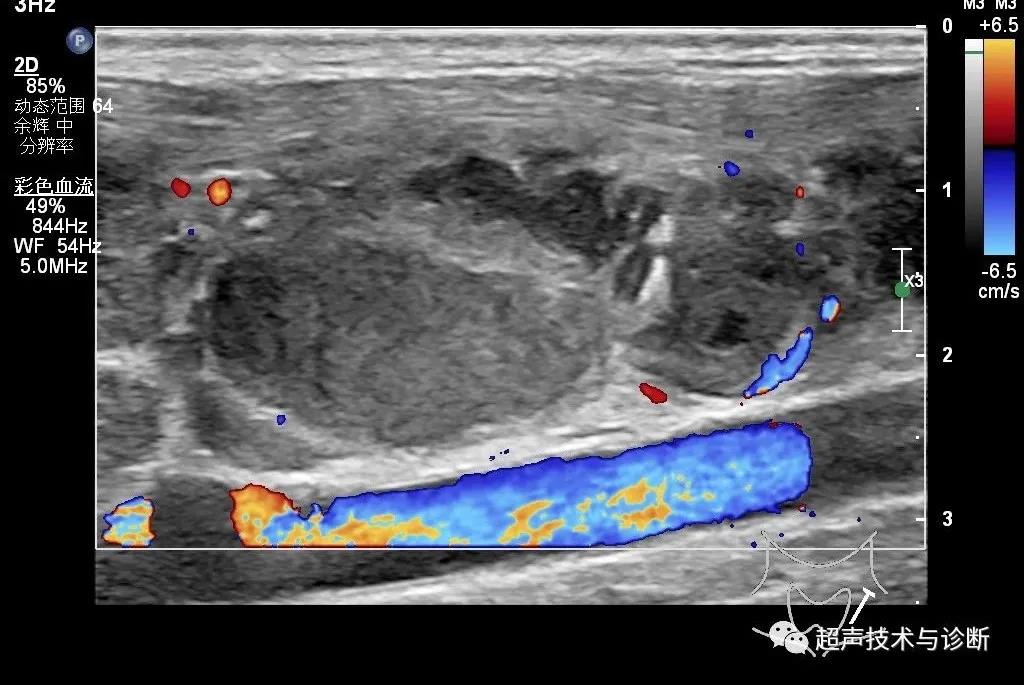

6、彩色多普勒超声显示病变淋巴结内的血流可呈偏心性的门型血流,约81%的结核性淋巴结炎有明显的占位效应和淋巴门血管异位。

7、结核性淋巴结炎的阻力指数(RI)<0.8,搏动指数(PI)在1.03~1.34之间。

1、超声上探及颈部多发的呈串状排列的肿大淋巴结,外形趋圆形,内部回声不均质,表现为低回声、无回声、强回声混杂,淋巴门偏移、狭窄或消失,淋巴结边界模糊,相互融合,彩色多普勒超声(CDFI)呈混合型,RI<0.8时应考虑结核性淋巴结炎可能。